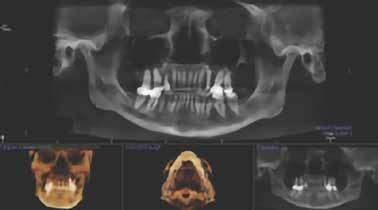

Optimális fogászati terápia obstruktív alvási apnoe esetén

Az optimális terápia sokban különbözik az elfogadhatótól, különösen a páciens szempontjából. Ez az esettanulmány rámutat a strukturális felmérés szükségességére a légutak 4 pontján, amelyet a kezelés megkezdése előtt a CBCT (i-CAT) alkalmazásával végezhetünk. Ezenkívül az esettanulmány bemutat egy súlyos obstruktív alvási apnoét egy olyan páciens esetében, akinél a folyamatos pozitív légúti nyomás (CPAP) csupán igen csekély hatással volt az állandó fáradtságára mindaddig, amíg a problémát nem kezelték orális alvásterápiás készülékkel megfelelően.

Esetismertetés

Egy 57 éves nőt 2012. augusztus 15én a háziorvosa utalt be rendelőnkbe. Fő panaszként fáradtságot, jelentős nappali aluszékonyságot, reggelente kialvatlan érzést, míg éjszaka gyakori ébredést tapasztalt és a CPAP-készülékkel való kezelést elviselhetetlen problémaként kezelte. Nyakának kerülete 37 cm volt, magassága 180 cm, testsúlya 91 kg, BMI 39,06, vérnyomás 116/117, pulzus 70, légzés 16, testhőmérséklet 36,6 °C Hosszú kórtörténettel rendelkezett: jobb csípőprotézis beültetése, jobb oldali agyműtét, amely során a szövetek és hipocampus eltávolításra kerültek, állcsontsebészeti műtét történt a mélyharapás és a keresztharapás korrigálására, számos elváltozás a szájban, amely a hátsó fogak csikorgatását eredményezte, valamint a páciens L–5 és S-I porckorongműtéten is átesett. Gyógyszeres kezelésben részesült magas vérnyomás, epilepszia, gastrooesophagealis reflux (GERD), migrén, osteoarthritis, pajzsmirigyproblémák, szorongás, depresszió és koncentrációs nehézségek kezelésére. ESS-pontszáma 14 volt. A beteg gyógyszerei a következők voltak: Nuvigil (stimuláns a túlzott nappali álmosság ellen) 250 mg naponta egyszer, Synthroid (pajzsmirigy-alulműködés ellen) 137 µg naponta egyszer, Lev-etiradcetam (Keppra) (görcsoldó gyógyszer a rohamok kezelésére) 1500 mg naponta kétszer, Trileptal (görcsoldó gyógyszer a rohamok kezelésére) 450 mg naponta kétszer, Viibryd (SSRI antidepresszáns) 40 mg naponta egyszer, Losartan (vérnyomáscsökkentő,

angiotenzin II receptor antagonista) 50 mg naponta egyszer, Nexium (protonpumpa-gátló, amely csökkenti a gyomorban termelődő sav mennyiségét) (GERD) 40 mg naponta, Intuniv (multivitamin) 4 mg naponta, és aszpirin 81 mg naponta egyszer. Klinikailag a nyelv az okkluzális sík fölött helyezkedett el, hiperkeratózis (B), a nyelv légutakba való behúzódása és Mallampati 4, amely mind minimális szájüregi térfogatra utalt (1–2. ábra). Ezek indikálták az alvásfogászati készülékes kezelést. Az izomtapintás elhanyagolható volt, és az állkapocs mozgástartománya is normális volt. A maximális nyitás 45 mm volt (1–2. ábra), oldalirányú elmozdulással 12, illetve 10 mm balra és jobbra. Az állkapocs normál mozgástartománya 42–52 mm volt maximális nyitás esetén, emellett oldalirányú elmozdulás 14 mm volt [13]. Az állkapocs ízületeinek dinamikus funkcióértékelését Joint Vibration Analysis (JVA [BioResearch]) segítségével végezték, és a lágy szövetek esetében a normál határokon belülinek, valamint kétoldali porckorongok perforációjának mentesnek találták (3. ábra)

A hipertrófiás gonialis szögek a felszíni masseter izmok kétoldali gyakori és folyamatos összehúzódásainak következményei, amelyek fokozott hypercapneával járnak együtt (megnő a CO a vérben) [14-15]. A hypercapnoe az OSAban a légzésre való ingerlés. A páciens gonialis szögének hipertrófiája jól látható volt a felvételen (6. ábra). Az okkluzális analízis II. osztályú volt, bruxizmusból eredő attrícióval. Standard fényképfelvételeket is készítettek (7. ábra). A páciensnél egy szakképesítéssel rendelkező alvásszakértő orvos poliszomnográfiát (PSG) alkalmazva súlyos OSA-t diagnosztizált. Apnoe/ hypopnoe-indexe (AHI) 79,9 volt (az AHI 30

tegek orális készülékterápiával (OAT) történő sikeres kezelésében [17]. Az orrlégúti elzáródás közvetlenül öszszefügg a nappali fáradtsággal [18]. Az i-CAT képalkotó szoftver lehetővé teszi az oropharyngeális légutak volumetrikus értékelését. Ennek a betegnek a kapott adatok alapján súlyosan veszélyeztetett légútja volt, minimum 61,3 mm-rel. A színskála azt mutatja, hogy az értékelés alsó határa 100 mm (9–11. ábra). Kezelési tervünkben OAT (EMA II), fül-orr-gégészeti konzultáció és egy nyomon követő alvásvizsgálat szerepelt. Az FDA által jóváhagyott alvásfogászati készülék 2012. szeptember 5-én került szállításra (12. ábra). A Sibilant Phoneme (Sziszegő fonéma) harapásregisztrációs technikát használtuk a készülék elkészítésének a kiinduló helyzeteként, mivel ez fiziológiai, nem pedig konstrukciós technika. Ez az egyetlen olyan harapásregisztrációs technika, amely bizonyítottan és szakmailag lektorált folyóiratban publikálva jelent meg. Ennek a harapásregisztrációs technikának lényege, hogy megnyitja a légutakat, de amely a legfontosabb, csökkenti azok összeesését [19]. Az OSA-ban szenvedő betegeknél a légzés kizárólag csak alvás közben áll le, ezzel szemben ébrenlét közben soha nem áll le. Így az oropharyngealis légutak térfogata kevésbé fontos, mint azok összeesése. Ez azt jelenti, hogy ritkán van szükség titrálásra, ha a fonetikus harapásregisztrációt kiindulási pontként használjuk. Ez a páciens tökéletes példa erre, mivel az ő készülékét soha nem kellett titrálni. Az orofaringeális térfogatok (13. ábra) az ébrenléti kiindulási állapotban és a harapásregisztrációval csak kis különbséget mutatnak, azonban az

7. ábra: Okklúziós analízis: II. osztályú bruxizmus okozta kopással. 8. ábra: Az elzáródás 4 pontjának diagramja (Brett Streed illusztrációja).